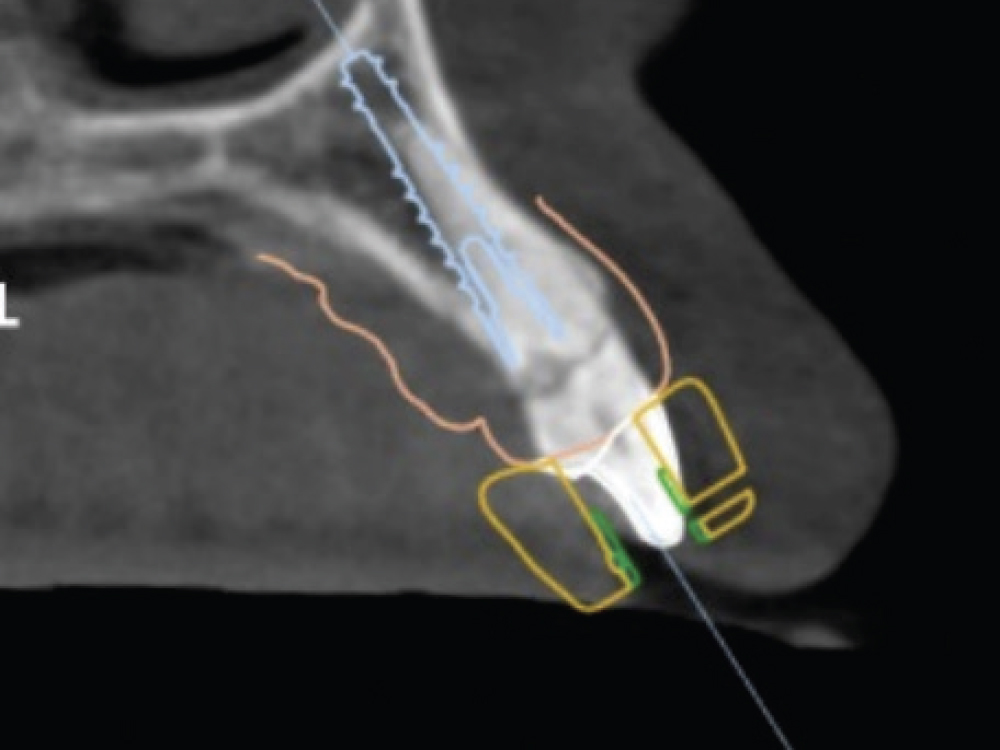

Figures 19a, 19b: The scan body was then registered with the IOS. With the soft tissue previously scanned and locked in place, there was no concern about the soft tissue collapsing while the scan body was being radiographed and its position captured.

As determined from the digital treatment plan prior to extraction and implant placement, a custom hybrid abutment and a cement-retained BruxZir® Esthetic crown were fabricated.

Figure 20: As determined from the digital treatment plan prior to extraction and implant placement, a custom hybrid abutment and a cement-retained BruxZir® Esthetic crown were fabricated.